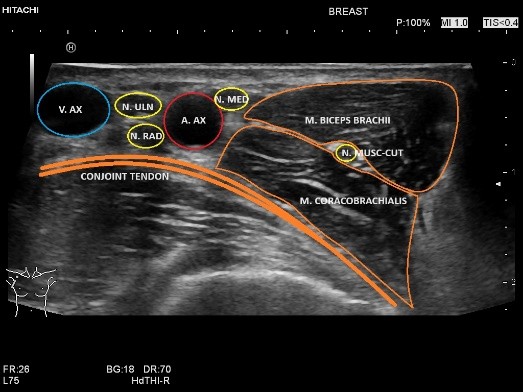

- Echografie van de zenuwen en AI:

In deze presentatie heb ik behandeld wat er nodig is voor degelijk echografisch onderzoek van de zenuwen. Een nauwgezette kennis van de anatomie en het kennen van de anatomische landmarks is een pré. Dit is getoond door de anatomie van de bovenste extremiteiten te laten zien en daarbij de onderzoeksmethode. Vanuit hier heb ik de raag gesteld waar AI ons vandaag de dag tegemoet kan komen middels de ontwikkelingen die er zijn. Zo kan AI de zenuwen herkennen en de overige weke delen, zoals spieren afgrenzen. AI kan bij dynamisch onderzoek de zenuw vervolgen en nauwkeurig een CSA meting doen. Daarnaast heb ik casuïstiek behandeld steeds in het licht van AI, met daarbij de vragen: is AI instaat bij verstoorde anatomie de zenuw te herkennen, herkent AI de pathologie zoals beknelling om compressiefactoren, zoals anatomische variatie en waar ligt het verschil/verantwoording van echografist en AI. Dat AI toekomst heeft is evident, deze ontwikkeling hou je niet tegen. Aan ons om steeds weer AI te controleren en ons voordeel er mee te doen.